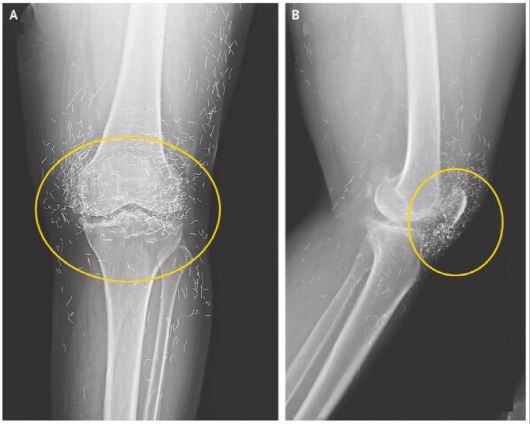

임상 의료분야 국제 학술지인 ‘뉴잉글랜드 의학 저널’에 소개된 65세 한국 여성 무릎 엑스레이 사진이다. (사진=‘뉴잉글랜드 의학 저널’) |

앞서 임상 의료분야 국제 학술지인 ‘뉴잉글랜드 의학 저널’에 65세 한국 여성 무릎을 촬영한 엑스레이 사진이 공개돼 화제를 모은 적이 있는데 당시에도 무릎 속에 수백 개의 바늘이 흩어져 있어 정체에 관심이 쏠렸고 이는 금침요법의 흔적으로 밝혀졌다.

이 여성은 평소 연골의 점진적인 손상으로 관절을 이루는 뼈와 인대에 염증과 통증이 생기는 퇴행성관절염을 앓아 항염증성 치료제 등의 약물요법을 받아왔다. 그런데 큰 효과가 없자 침술요법 쪽으로 치료방식을 바꿨다. 저널은 그녀가 여러 침술 치료 중 ‘금침 요법’을 받았다고 전한다.

통증 완화를 위해 계속 침을 주입하다 보니 어느새 개수가 수백 개가 넘었고 이것이 고스란히 무릎 속에 남게 된 것이다.

저널에서 미국 보스턴대학 방사선과 알리 게르마지 교수는 몸속에 이물질이 남아있는 경우, 염증 악화와 2차 감염 등으로 이어질 수 있어 무척 위험하다고 주장한다.

그는 “신체는 이물질이 들어오면 이를 제거하려는 방어 작용을 수행하기에 해당 과정에서 염증 등이 발생할 수 있다. 또한 침들이 몸속을 돌아다니면서 동맥과 같은 중요 부위를 손상시킬 수도 있다”고 강조했다.